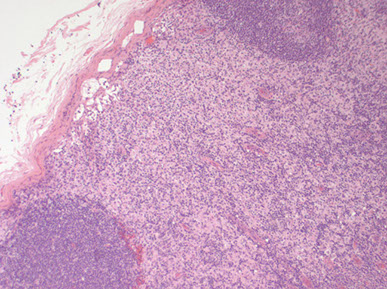

Reactive follicular hyperplasia (arrow to focal paracortical hyperplasia) [2]

Reactive Follicular Hyperplasia (RFH). Follicles (B-cell compartment) have varying size and are well spaced from one another. There is a nice capsule and subcapsular sinus. In medullary compartment where plasma cells and memory B-cell live, the sinuses are open and patent. Note the relative abundance of the paracortex compared to the cortex, which is an important feature for B9 LNs.

Hyperplastic lymphoid follicle. Germinal center with sharply demarcated mantle zone (solid blue arrow). Dark zone of GC with starry-sky pattern (open blue arrow) and light zone (open black arrow) with small centrocyte predominance [2]

High magnification of GC with centroblasts (solid blue line) mixed with histiocytes with clear cytoplasm with nuclear fragments (open black line) and frequent mitoses (curved black line)